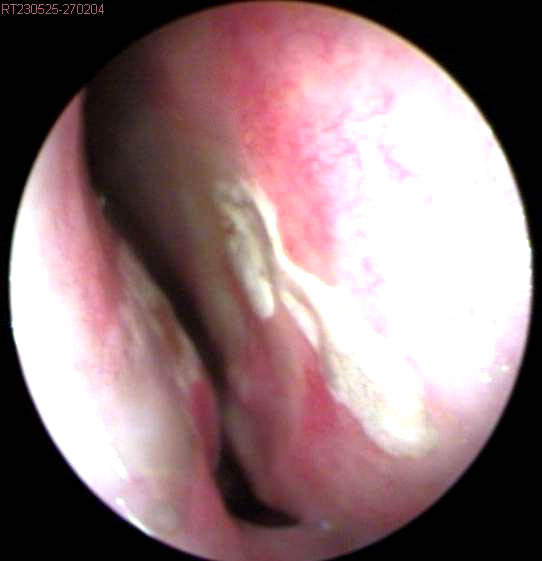

JFC otopatía supurativa crónica inactiva (der) y con colesteatoma atical (izq)